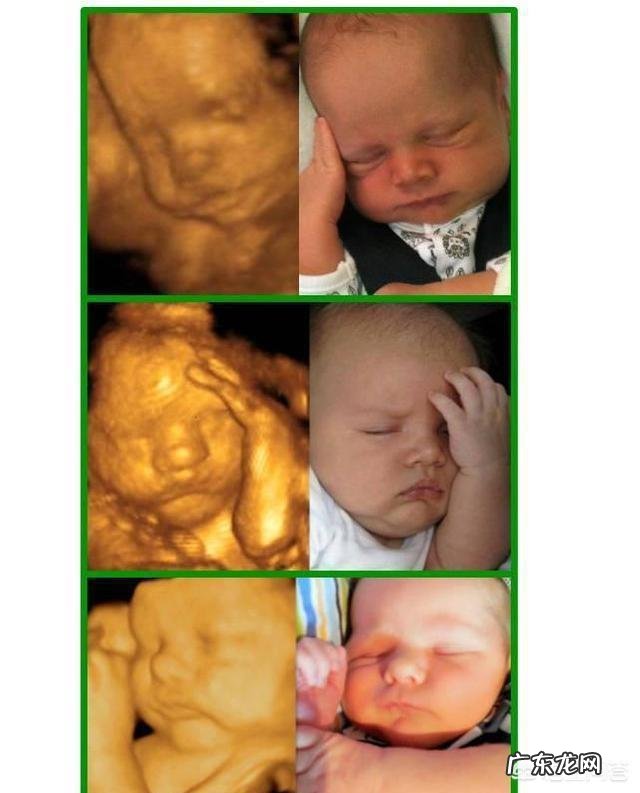

当然也会有一些准妈妈们会有题主一样的疑问,就是孩子生出来是不是会跟四维照片一样啊,是不是会很丑啊之类的,我告诉你,完全不必担心,因为自己的娃随着慢慢长大,怎么看怎么爱 。

总之,B超出来的照片跟实际生出来之后是有很多差别的 。咱就不说这个,就说孩子长大和小时候吧,差别一般都是蛮大的,所以,不用纠结这个B超的样子,再说了,现在的宝宝营养充足,出生后基本都白胖的,肯定不会难看的,放心吧 。

过来人都知道,新生宝宝像个小老头,丑丑的,但是不久之后,宝宝就会发生很神奇的变化,完成丑小鸭到白天鹅的巨变 。